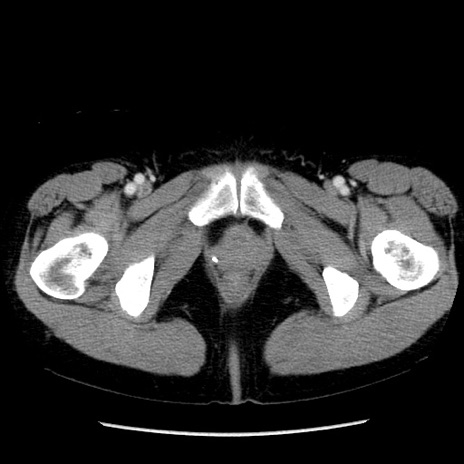

症例6(横断像)

【症例】50歳代女性

【主訴】下腹部痛

【現病歴】本日朝より下痢2回あり。 昼食を食べた後、嘔吐3回、下腹部痛認め、症状軽快せず、当院救急搬送。

最終食事:本日昼(生ものなし)。 昨日の夜、刺身を食ぺたとのこと。周囲に同様の症状の者なし。普段、排便は毎日あるとのこと。

【既往歴】卵巣癌術後(8年前に当院で卵巣摘出)

【身体所見】 意識清明、腹部:平坦、腸蠕動音→、やや硬、下腹部自発痛・圧痛あり、反跳痛あり、筋性防御なし。

【データ】WBC 16000、CRP 0.01